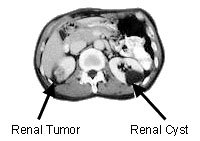

Kidney http://www.mskcc.org/cancer-care/adult/kidney/about-kidney

There is no evidence or consensus

on baseline screening for Kidney cancer at this time.

Advanced kidney cancer screening may take the form of genetic testing if there is a corroborating family history of the disease. http://www.cancer.net/cancer-types/kidney-cancer/risk-factors-and-prevention Genetic testing may indicate a higher risk of getting kidney cancer.

Screening in the form of imaging studies like X-ray, CT scan, and MRI may follow the symptomatic pursuit of causes for hematuria, swelling in the abdomen, as well as swelling in the lower extremities. A biopsy may also be performed to confirm a finding.